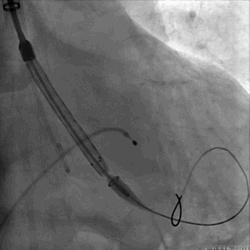

瓣膜释放DSA

最后一枪造影

术后:

瓣膜功能良好,患者反流消失,颈动脉阻断时间12分钟,患者术后顺利苏醒,无脑血管并发症,一周后顺利出院。